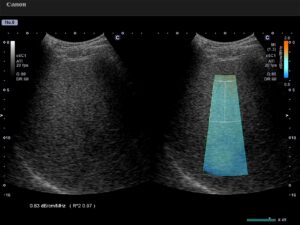

↑こちらは肝臓の脂肪化を測定している画面です。

特徴は、肝臓の脂肪量を測定する機能ATI(Attenuati